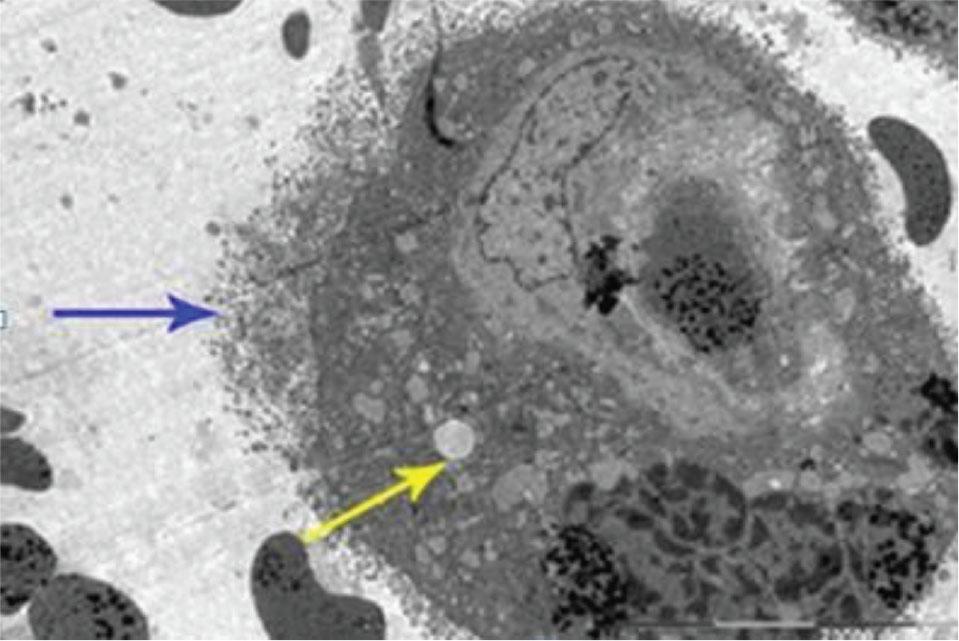

Ultrastructural findings of cells in the placental villi of HELLP group. In the placental sections of the HELLP group, intracytoplasmic edema, degenerative vacuoles and degenerative findings in cell surface membranes were observed in syncytiotrophoblasts. In addition, villous edema was prominent. In another placenta section of the same group, as well as intravascular coagulation, presence of red blood cells in the extravascular areas due to endothelial degeneration, thinning of the capillary endothelium, villous edema, and degenerative vacuoles were observed (Figure 3).

Ultrastrucutural placenta section of HELLP group. Degenerative structure (blue arrow) in cell surface membrane, intracytoplasmic edema, and degenerative vacuoles (yellow arrow) in syncytiotrophoblast(lead nitrate-uranyl acetate, Bar: 20,000 nm). HELLP, hemolysis, elevated liver enzymes, low platelet count.